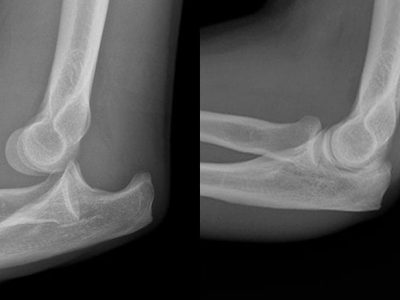

The elbow joint is a type of hinge joint. It bends (flexion) and straightens (extension), as well as rotating to position your palm up or down. The normal range of flexion and extension is from 0 to 145 degrees, although…

What is a Simple Elbow Dislocation? Simple Elbow Dislocation: This happens when the elbow joint (where the upper arm bone meets the forearm bones) gets dislocated without any broken bones. Complex Instability: This occurs when there are broken bones along…